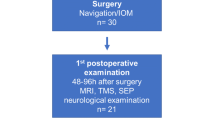

The NBS System 4 became available to us in October 2010. The first 30 consecutive patients with lesions in or adjacent to the primary motor cortex were enrolled in this study. No patient had to be excluded. Most common entities were astrocytoma (30 %), followed by metastasis (20 %) and meningioma (17 %) (Table 1). The patient’s age ranged from 2 to 76 years (median, 54 years). Ten patients (33 %) presented with a preoperative hemiparesis.

nTMS was feasible in all 30 cases. fMRI was impossible in 7 of 30 cases (23 %). In two patients, this was due to an impaired cooperation (dementia in case No. 1 and severe frontal lobe syndrome in case No. 11). Two patients were too young (age 2 and 3 years) to perform the motor paradigm (case No. 4 and 7). Two patients suffered from aphasia and apraxia (case No. 10 and 19) while one patient was hemiplegic (case No. 2), which rendered the motor task impossible (Table 2).